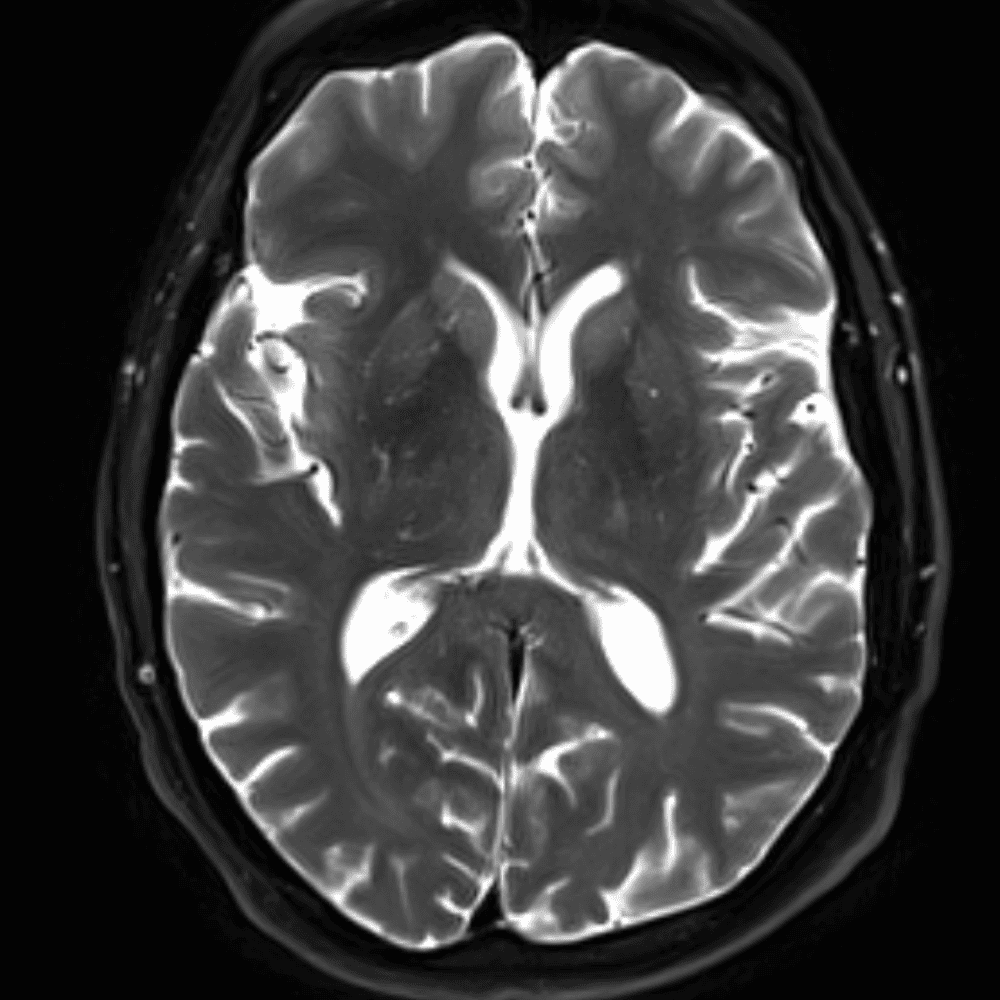

๋‹น์ง ์‹œ ํ”ํžˆ ๋ณผ ์ˆ˜ ์žˆ๋Š” ์‚ฌ๋ก€์˜ ์ „ํ˜•์ ์ธ ์˜ˆ๋ฅผ ํฌํ•จํ•ฉ๋‹ˆ๋‹ค.

39 ์‚ฌ๋ก€